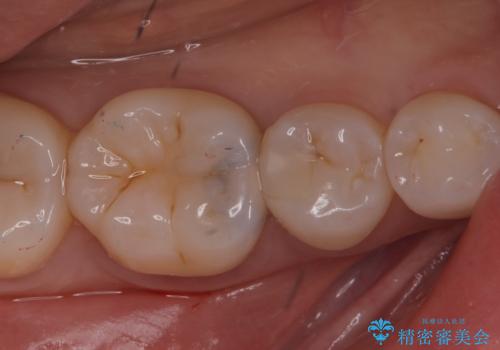

- 主訴:右下の奥歯がたまに冷たい物や甘いものでしみる

右下6番目の歯に大きめのう蝕を認め、形態の再現性を考えインレーでの治療となりました。

右下6の近心にう蝕が認められう蝕の範囲が大きかったため、歯冠形態の再現性の高いインレーでの修復とし、材質は審美性、清掃性に優れたセラミックを選択しました。